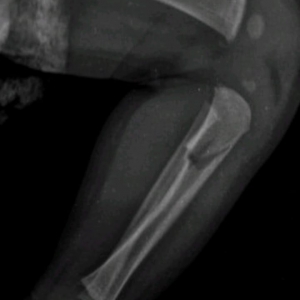

Na manhã desta segunda-feira (07) a 20ª Subdivisão Policial de Toledo divulgou o resultado das investigações acerca de uma tentativa de homicídio praticada contra um bebê, na época com aproximadamente 40 dias, onde os pais do infante eram os suspeitos.

O caso ocorreu no início do mês de julho, sendo os pais investigados inicialmente presos temporariamente por 30 dias.

Durante este período as investigações transcorreram e foi possível reunir ainda mais evidências do envolvimento dos pais da criança no caso, fato este que ensejou representação pela Prisão Preventiva, a qual foi determinada pelo Poder Judiciário, seguindo os pais da criança (21 e 22 anos de idade) agora presos por tempo indeterminado enquanto aguardam o andamento do Processo.

O Delegado Rodrigo Baptista Santos disse que "a postura dos investigados em sustentar uma versão absurda para os fatos constatados, dizendo que não tinham notado os hematomas, os quais surgiram repentinamente, acreditando serem reações alérgicas de uma picada de mosquito, caíram por terra com os Laudos e exames que atestam a gravidade das lesões e o risco a vida do qual o infante foi exposto".